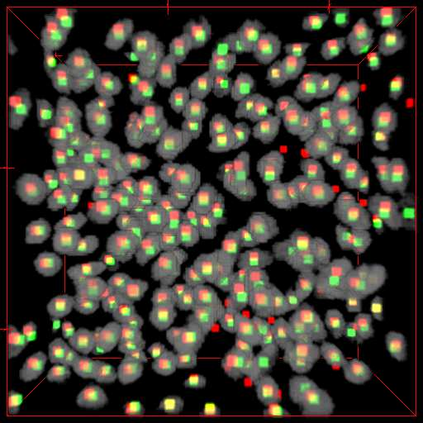

Robust and accurate nuclei centroid detection is important for the understanding of biological structures in fluorescence microscopy images. Existing automated nuclei localization methods face three main challenges: (1) Most of object detection methods work only on 2D images and are difficult to extend to 3D volumes; (2) Segmentation-based models can be used on 3D volumes but it is computational expensive for large microscopy volumes and they have difficulty distinguishing different instances of objects; (3) Hand annotated ground truth is limited for 3D microscopy volumes. To address these issues, we present a scalable approach for nuclei centroid detection of 3D microscopy volumes. We describe the RCNN-SliceNet to detect 2D nuclei centroids for each slice of the volume from different directions and 3D agglomerative hierarchical clustering (AHC) is used to estimate the 3D centroids of nuclei in a volume. The model was trained with the synthetic microscopy data generated using Spatially Constrained Cycle-Consistent Adversarial Networks (SpCycleGAN) and tested on different types of real 3D microscopy data. Extensive experimental results demonstrate that our proposed method can accurately count and detect the nuclei centroids in a 3D microscopy volume.